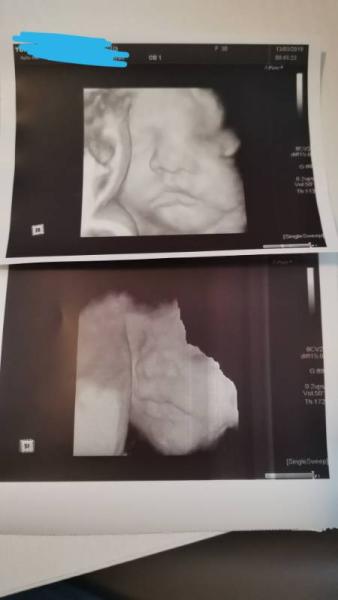

Hallo ihr lieben. Wir hatten heute wieder einen Termin zum Ultraschall und das erste Mal durfte auch mein Mann mit - mit Negativem Test Der kleine scheint kerngesund zu sein und war aber leider nicht besonders kooperativ Sie sagte er sei sehr groß und hat sehr lange Beine. bin heute bei 25+5 und er wiegt 960 gramm. Leider scheint meine Vaginal Flora total aus dem Gleichgewicht zu sein. ich musste deswegen im Jänner bereits eine Antibiotika Kur machen und anschließend mit Milchsäure Bakterien.. hat wohl nicht geholfen. muss ich jetzt nochmal machen aber länger. was ich echt witzig fand war dass ich das Gefühl habe das sich meine Jungs SEHR ähnlich sehen ich hab euch mal die bilder von heute angehängt und danach einen Vergleich der beiden. das obere Bild ist der große und das untere von heute. Unterschied in der Zeit sind ~5/6 Wochen. was sagt ihr?

und hier der Vergleich der Jungs

Die zwei sehen aus wie Zwillinge!!! Wahnsinn Ich freue mich, dass bei deinem Kleinen alles in Ordnung ist und, dass er prächtig wächst! Das ist wirklich das wichtigste und deine Problemchen da unten kriegst du bestimmt noch im Griff Schön auch, dass dein Mann mitdurfte!!! Ich finde es echt wichtig, dass die Papas auch die Termine beim Frauenarzt erleben. Ich habe echt Glück, meine Frauenärztin sieht es genauso und lässt die Männer rein